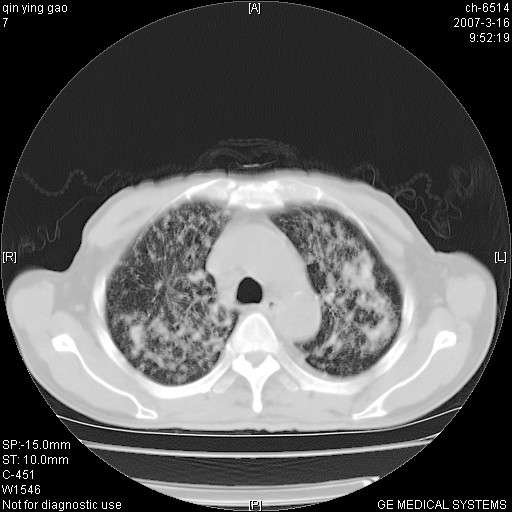

男,64岁.乏力2个月,畏寒、发热1月余。体重下降。血沉加快,白细胞不高。

两中上肺见有广泛新老不一的结节灶,并伴有纤维索条影,血沉加快,白细胞不高,首先考虑结核。

双肺以中上肺野为著斑片状.结节壮密度增高影 左上肺前段可见小类圆钙化灶 纵隔淋巴结无明显肿大

双肺可见大小不等结节状密度增高影,密度不均,分布不均(双肺上叶为著),亚急性血行播散性肺结核.

(本例特征:以大小不等结节为主,主要分布在双上肺,并部分病灶融合成较大结节,期间搀杂诸多细小结节。从病灶特点与分布形式分析,更趋向于感染。)

男,64岁.乏力2个月,畏寒、发热1月余。体重下降。血沉加快,白细胞不高。 双肺可见大小不等结节状密度增高影,密度不均,分布不均(双肺上叶为著),亚急性血行播散性肺结核.

中上肺野密布棉团状影,以胸膜下区为界,边缘模糊,可能是小叶或腺泡渗出及实变。全肺野弥漫分布网线样影及细小粟粒样影,可能是细支气管炎及间质内炎症。综合分析应首先考虑气道播散性感染,而肺内多处斑点性钙化,强烈提示陈旧结核复发并支气管播散。建议详细讯问病史